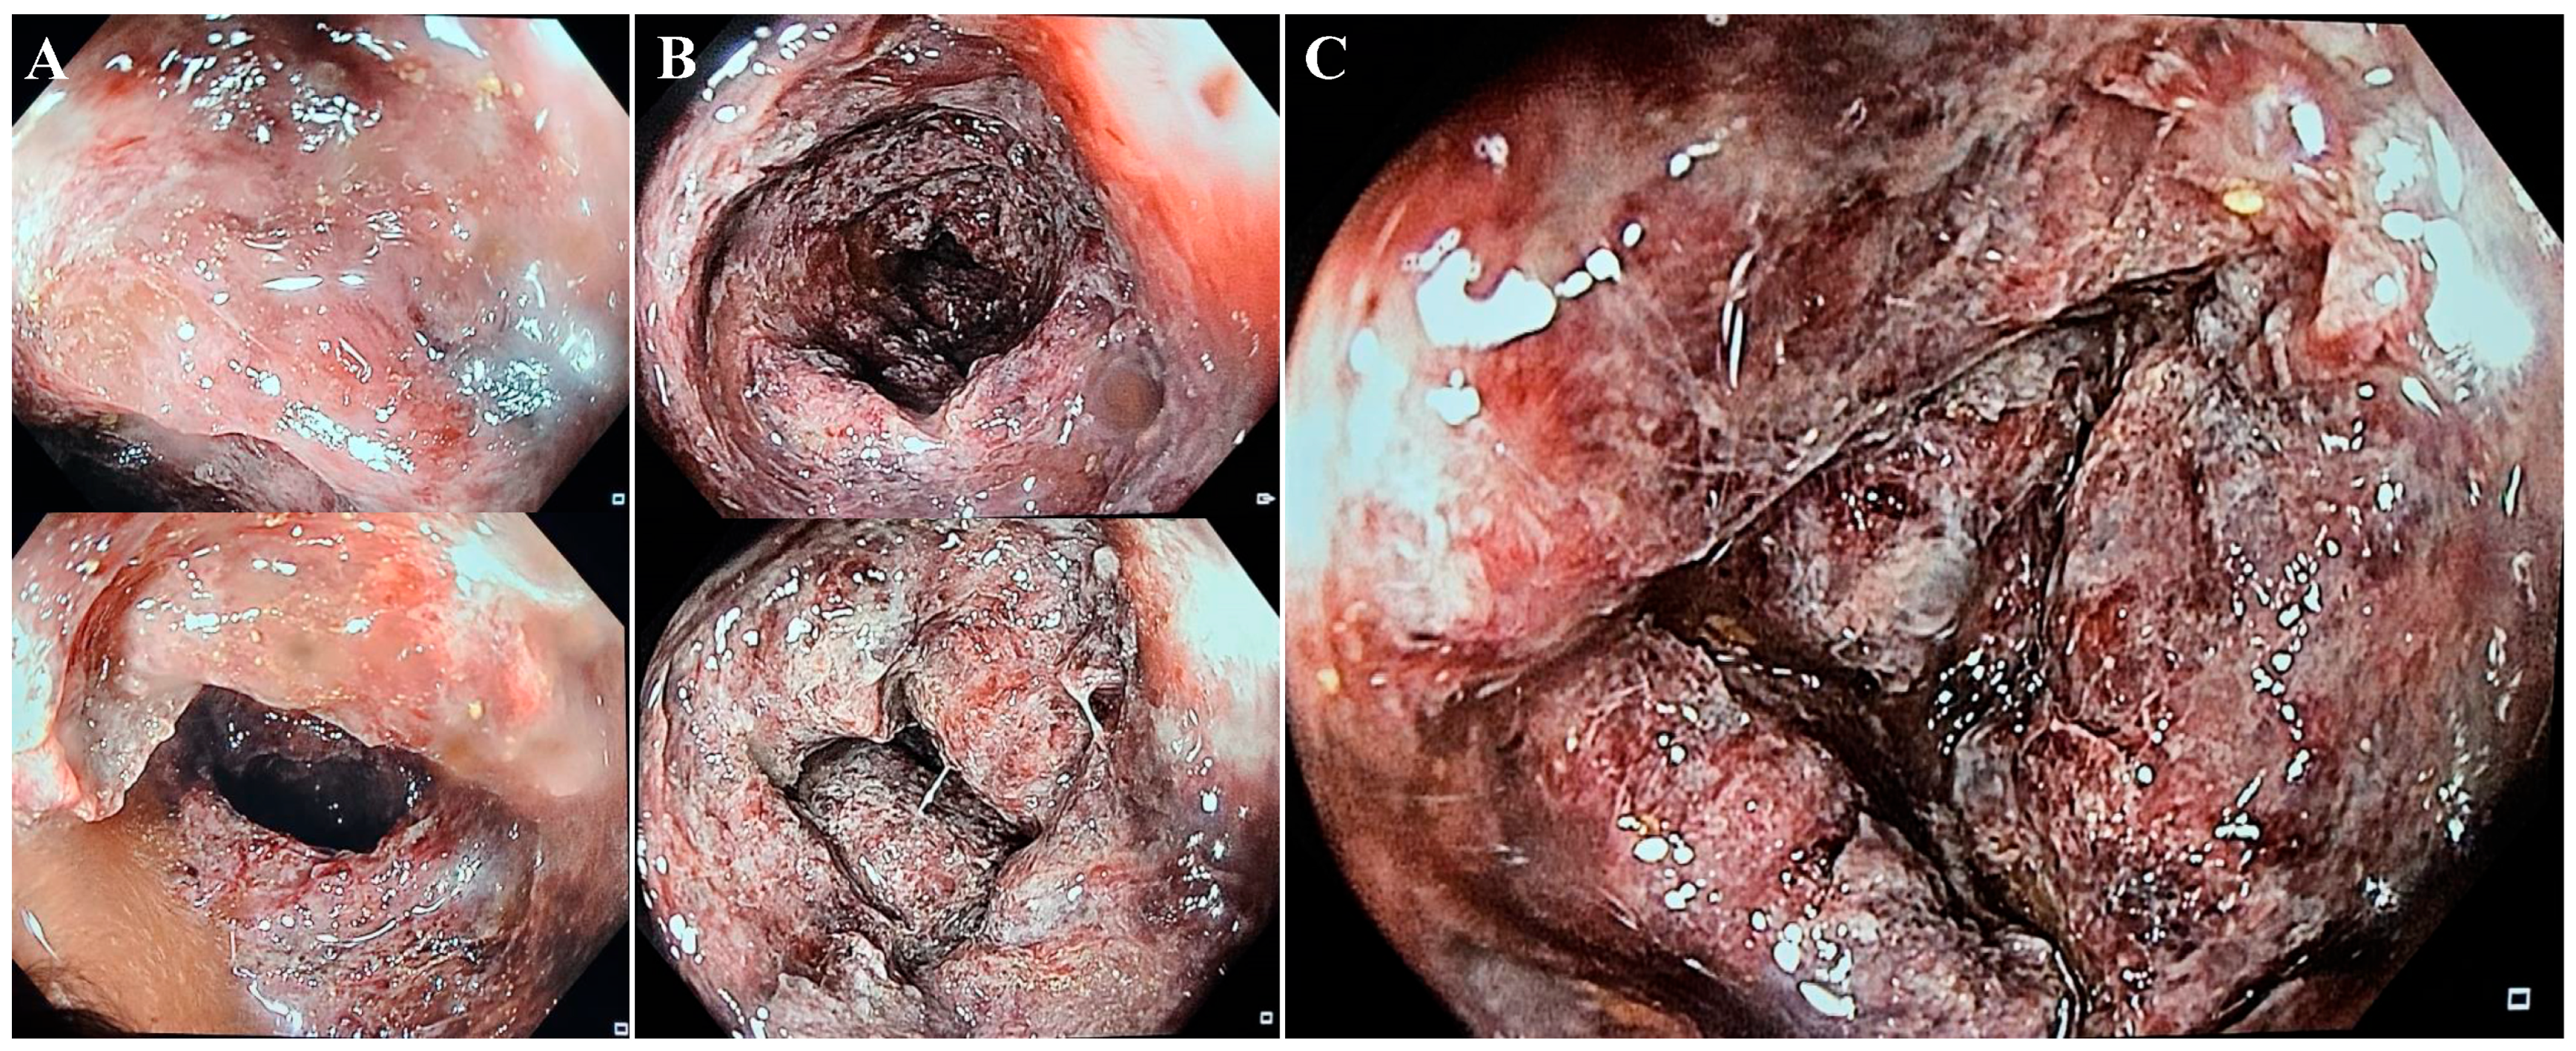

On the second day, the patient underwent a colonoscopy that revealed a less-affected sigmoid colon, with deep ulcerations, dusky areas, and necrotic lesions in the ascending colon, as well as friable mucosa located 40–60 cm from the anal canal (Figure 3), an atypical picture for inflammatory bowel disease. Because of the friability of the damaged mucosa, the gastroenterology specialist could not advance any further through the transverse colon with the colonoscope.

Rectoscopy or colonoscopy and tissue biopsies complete the investigational plan for achieving a positive diagnosis. In our case, although the entire colon was affected, the endoscope could reveal no further than 40–60 cm from the anal canal because of the risk of iatrogenic colon perforation. Histological biopsies from the colon or rectum may show similar patterns to those in ischemic colitis, such as atrophic crypts, coagulative necrosis of the mucosa, hyalinized lamina propria, and fibrin thrombi [6].

Figure 3. Sigmoid colon—quasi-normal aspect with erythematous lesions and hemorrhagic debris (A). Descending colon—sections of erythematosus mucosa, with multiple ulcerations (B). Descending colon at 60 cm from anal canal—deep ulcerated lesions and friable, hemorrhagic mucosa (C).